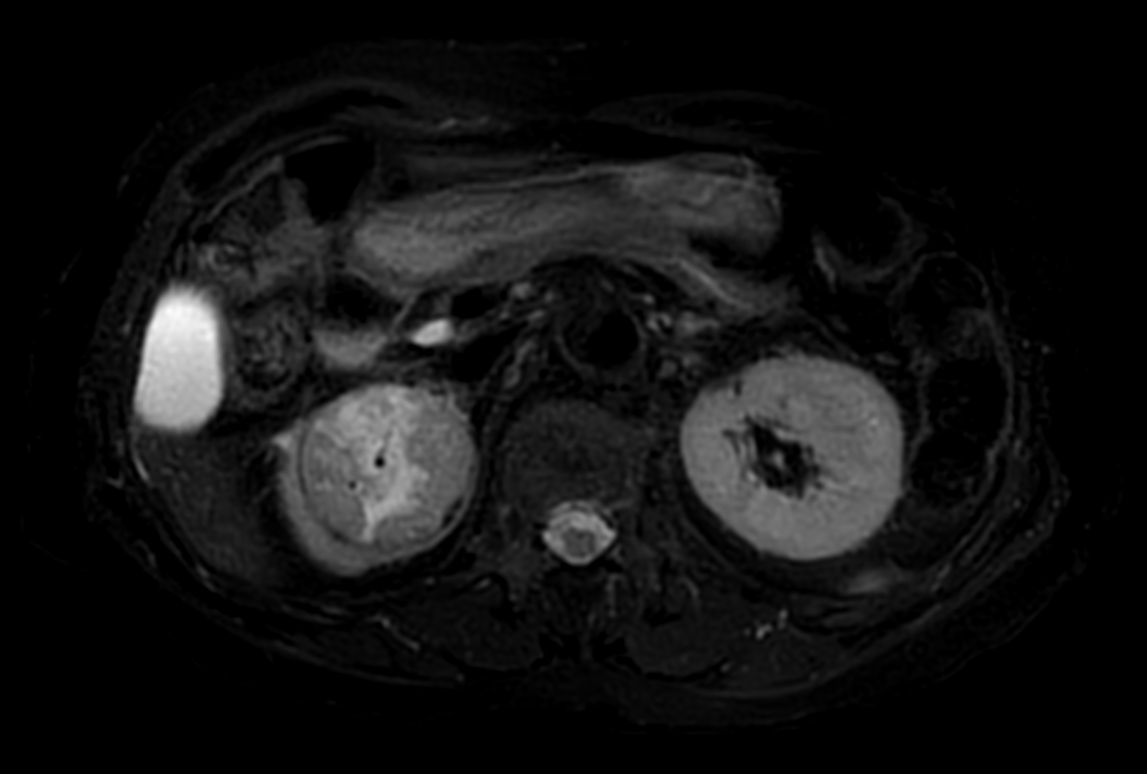

Patient with a kidney lesion. The ExamCard includes techniques for 3D imaging (PelvisVIEW, eTHRIVE) allowing for multiple image directions in one single scan, efficient fat-free imaging over large field-of-views (mDIXON XD), a multi-phase contrast-enhanced sequence (4D FreeBreathing) to improve imaging confidence and Compressed SENSE to accelerate the entire exam.

DWI b800